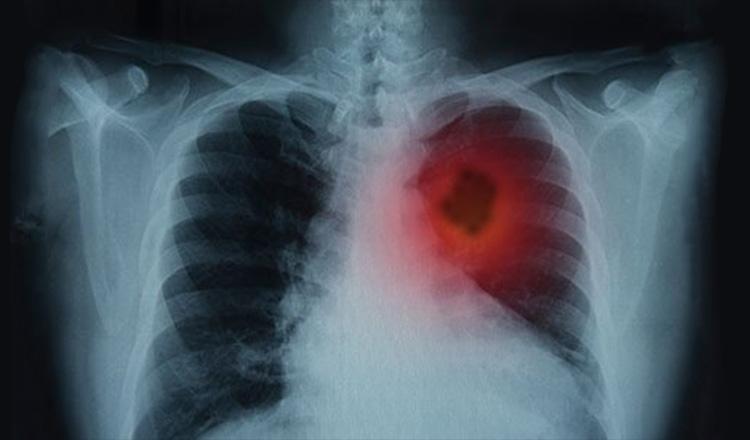

ফুসফুসের ক্যান্সারের প্রাথমিক লক্ষণ

ক্যান্সার থেকে মৃত্যুর অন্যতম প্রধান কারণ ফুসফুসের ক্যান্সার। এর একটি কারণ হলো প্রায়শই খুব বেশি দেরি হওয়ার আগ পর্যন্ত মানুষ তাদের ফুসফুসের ক্যান্সার সম্পর্কে জানতে পারে না।